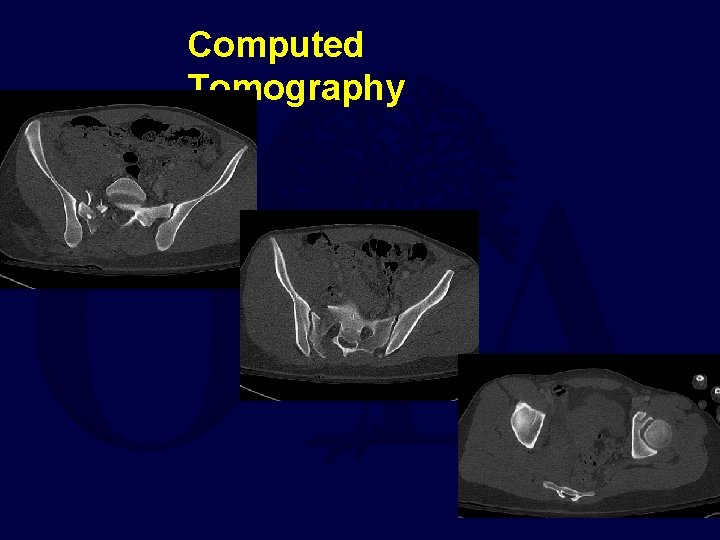

Computed Tomography

Computed Tomography L 4 and L 5 Nerve Roots run here